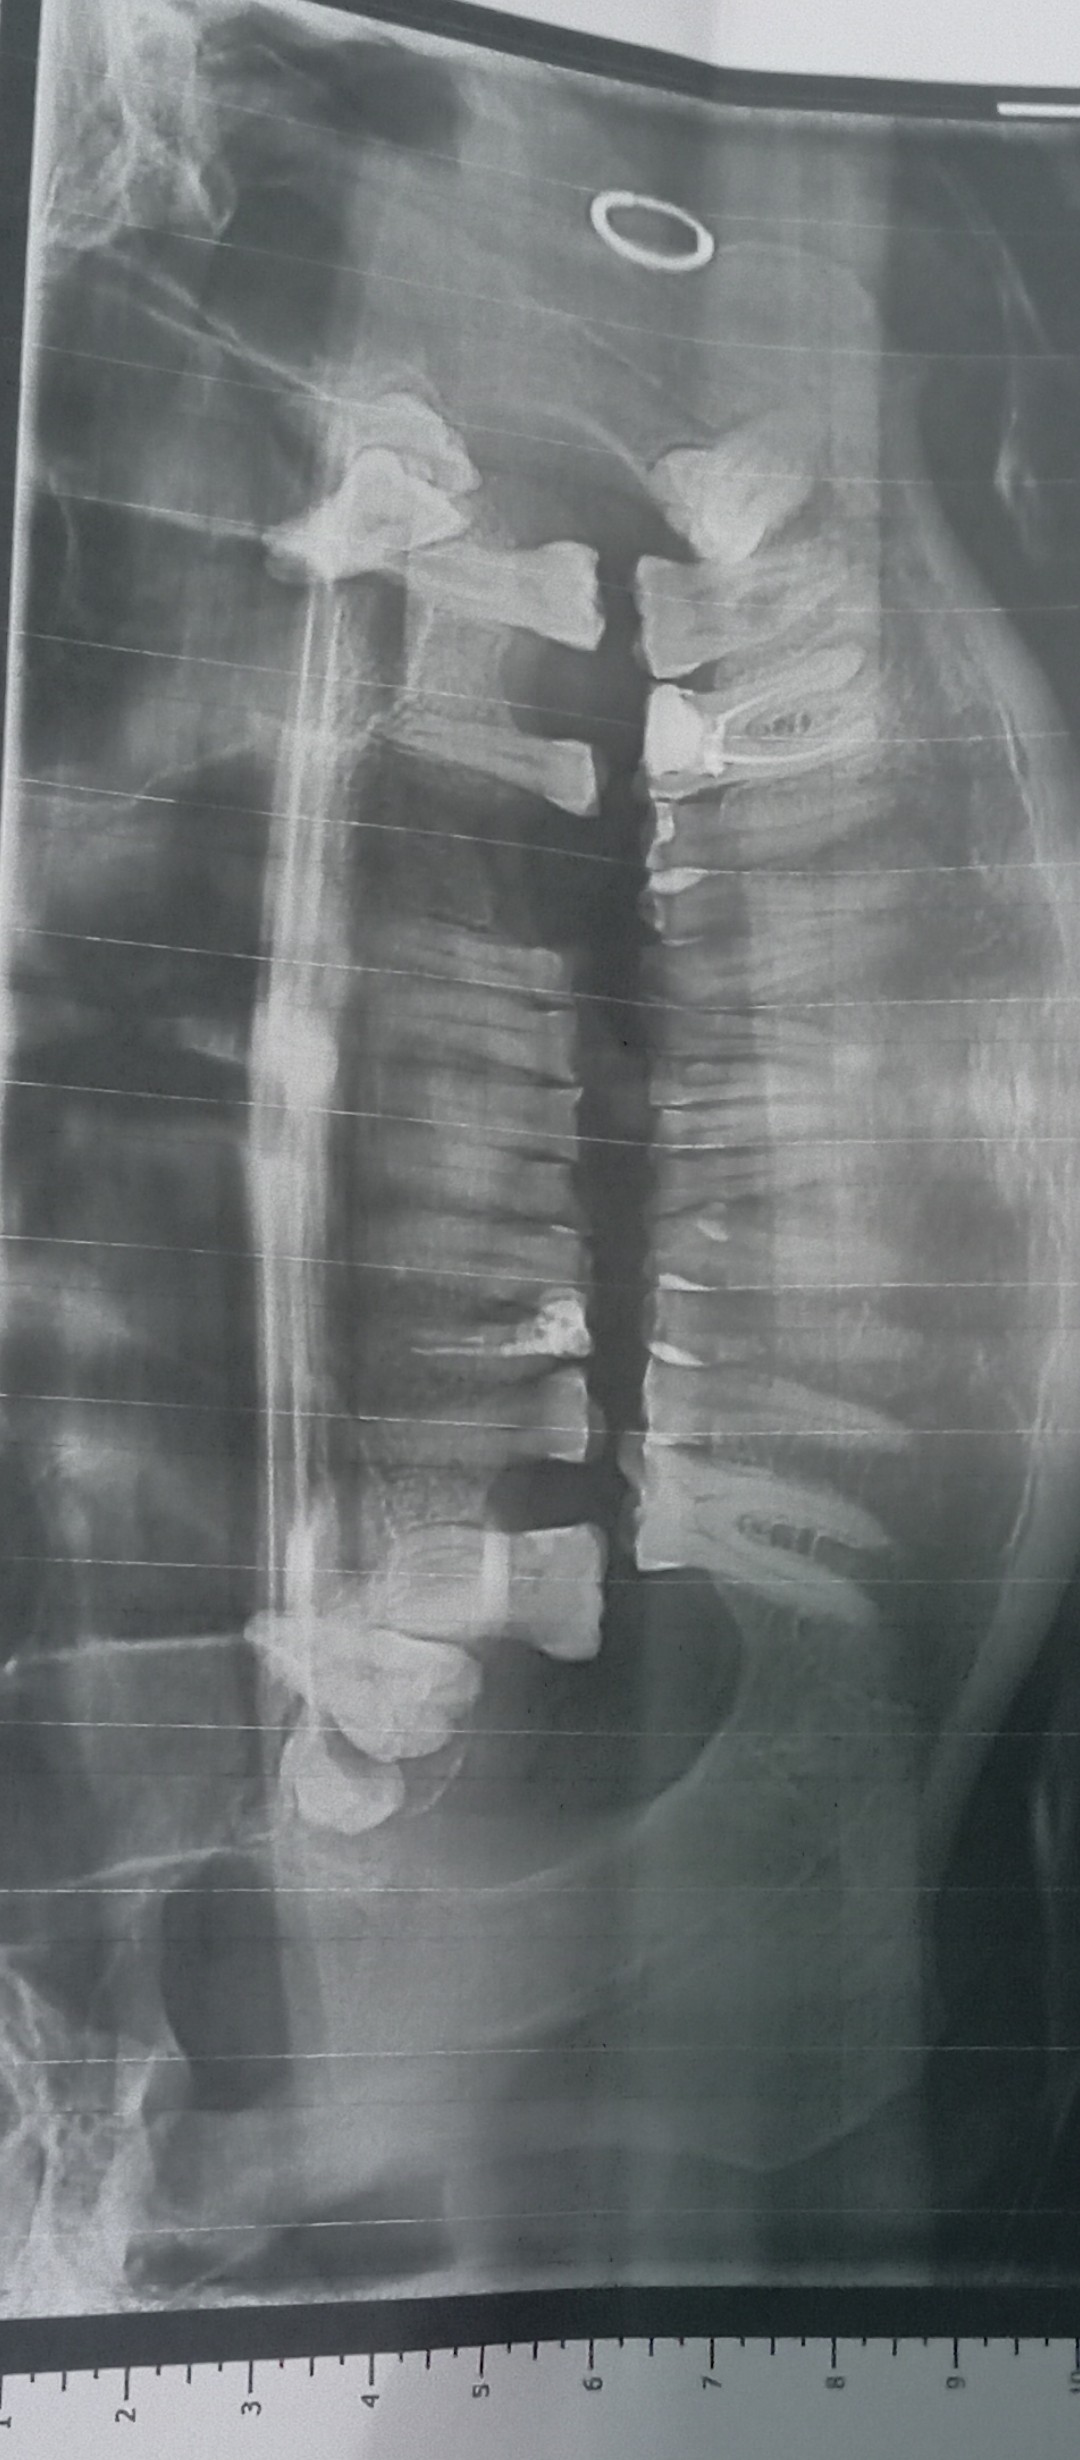

Добрый день. Неделю назад у меня начала болеть десна в нижнем ряду за седьмым зубом. Там как бы ранка Толи трещина и подпухло немного. Та восьмерка следит крепко. Мне 46 доктор говорил шо она уже не выйдет. Так вот через пару дней добавилась боль в шестом или седьмом зубе. Пульсирующая боль. Ночью не спал почти. Утром сегодня поехал к хирургу он удалил шестой зуб так как он плохой на снимке. Теперь я думаю решил ли я проблему, или это будет продолжаться и в е это из-за восьмёрки? Как думаете на снимке есть восполнение которое давало боль? Спасибо